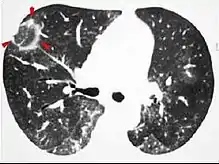

.jpg.webp) CT image showing diffuse GGOs throughout both lungs. An abscess is also noted in the right lung (screen left).

CT image showing diffuse GGOs throughout both lungs. An abscess is also noted in the right lung (screen left). - Adenocarcinoma in situ of the lung